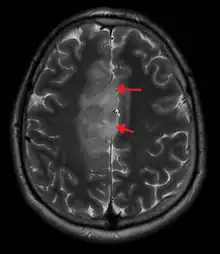

An X-ray computed tomography (CT) or magnetic resonance imaging (MRI) scan is necessary to characterize the anatomy of this tumor as to size, location, and its heter/homogeneity. However, final diagnosis of this tumor, like most tumors, relies on histopathologic examination (biopsy examination).[3]